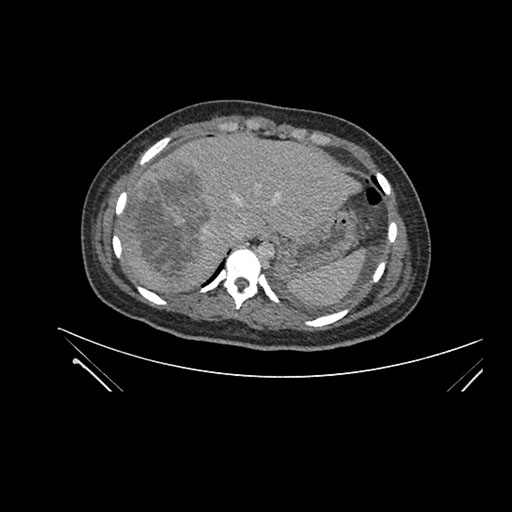

Imaging Analysis

Look through the patient's CT scan to identify any areas of concern for the necessary procedure.

Axial Venous

Based on initial findings, which issue(s) would you be most concerned about?